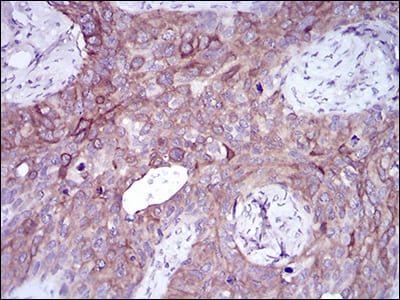

| IHC | 1/200 - 1/1000 | Human,Mouse,Rat |